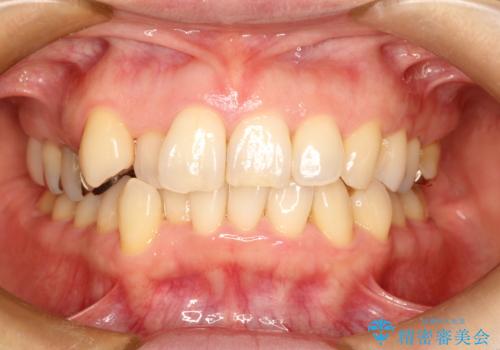

前歯の突出を防ぎながらガタつきを解消。上下左右4番抜歯による審美ワイヤー矯正

担当医 河口智英